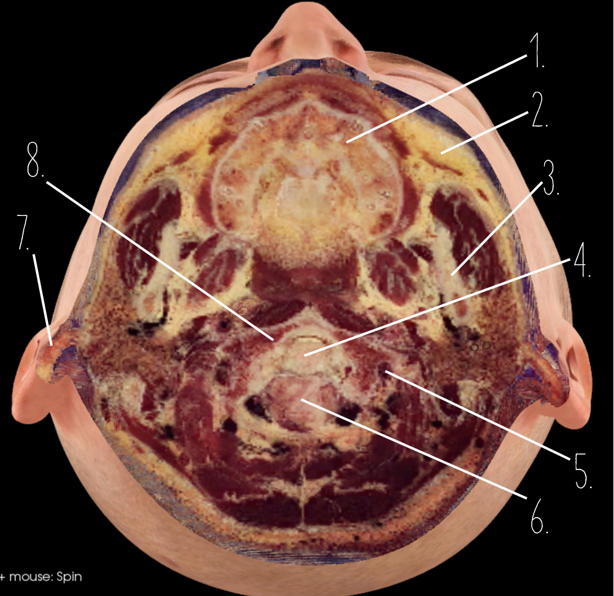

1?

Nasal Bone

2?

Maxillary Sinus

3?

External Acoustic Meatus

4?

Pons

5?

Cerebellum

6?

Mastoid Air Cells

7?

Mandibular Condyles

8?

Sphenoid Bone

9?

Maxillary Bone